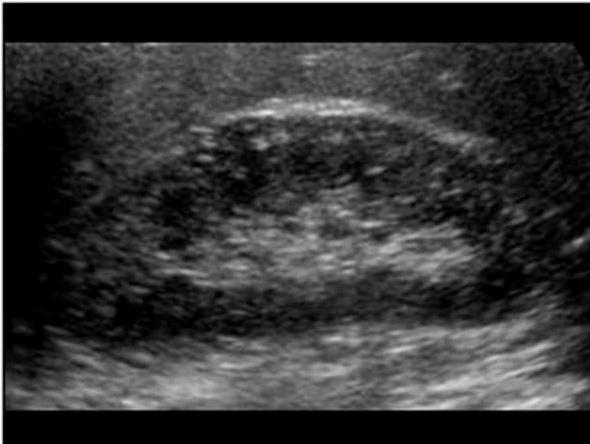

Wilm's Tumor

3 years